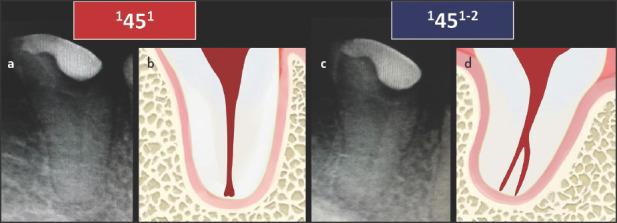

Adequate understanding and accurate characterization of normal and unusual root and canal morphology are essential requirements for successful root canal treatment. A new coding system for classifying root and canal morphology, accessory canals and anomalies has been introduced. In addition to technological advances related to experimental studies involving micro-computed tomography, the continuing clinical advances in magnification, illumination, imaging and intra-operative root canal treatment procedures have allowed clinicians to identify an increasingly wide range of anatomical variations in roots and canals in an attempt to achieve more predictable clinical outcomes. This review aims to provide a step-by-step explanation for the clinical application of the new coding system in dental practice, and to describe the anatomical variations in roots and canals for teeth scheduled for root canal treatment.

充分理解和准确描述正常和异常的牙根和根管形态是根管治疗成功的基本要求。引入了一种新的根管形态、副根管和异常分类编码系统。除了与涉及微计算机断层扫描的实验研究相关的技术进步外,放大、照明、成像和术中根管治疗程序的持续临床进展使临床医生能够识别越来越广泛的根和根管的解剖变异,试图实现更可预测的临床结果。本综述旨在为新编码系统在牙科实践中的临床应用提供逐步解释,并描述计划进行根管治疗的牙齿的牙根和根管的解剖变异。